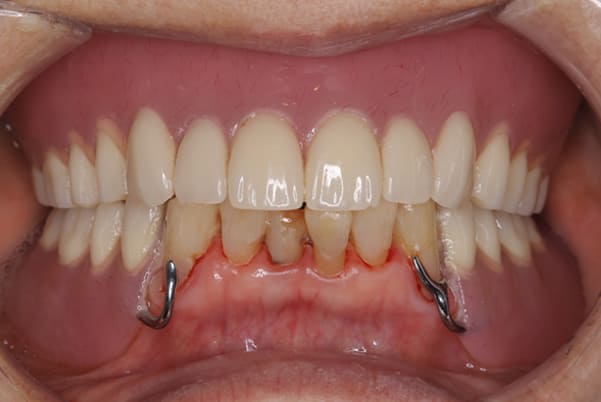

治療前後の口元の比較

こちらは、口を少し開いた時の治療前と治療後の

口元です。

正面から見た時にクラスプが目立たないように、

歯ぐきになじむ素材にて入れ歯を製作し、痛くなく自然に馴染み快適に生活を送れるようになりました。